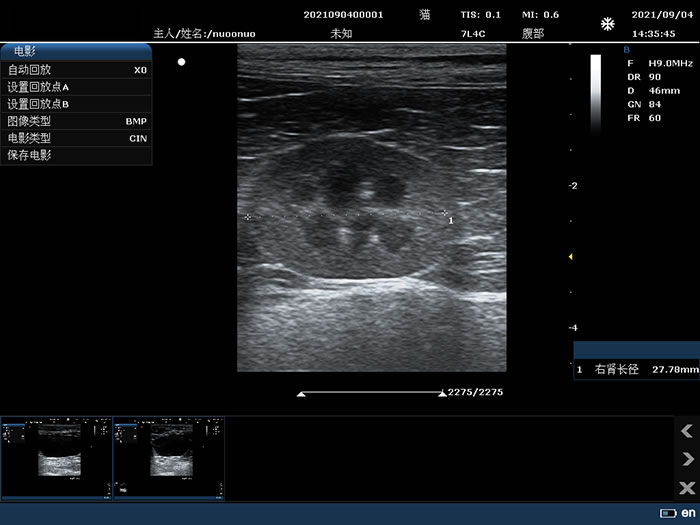

小器官B模式应用测量

7L4C: 7.5MHz/L38mm/128阵元线阵探头;